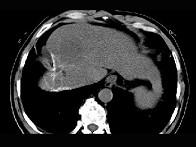

问题 女性,56岁,腹胀、双下肢水肿、乏力、食欲不振,影像所见如下图,最佳的诊断是 ( )

选项 A.酒精性肝硬化并肝血管瘤 B.血吸虫肝硬化并肝癌 C.肝炎后肝硬化并肝癌 D.局限性脂肪肝 E.原发性肝癌

答案 B